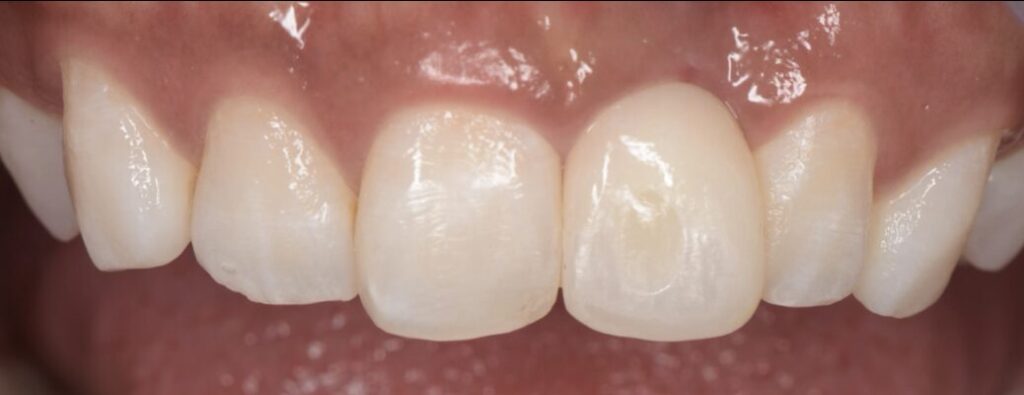

After

インプラントSET後の口腔内写真とデンタルX線写真